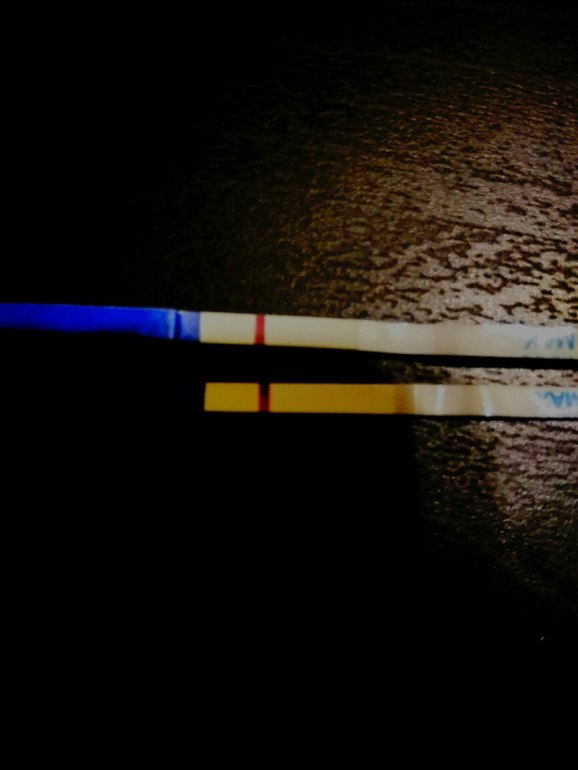

Здравствуйте девушки. Был укол Овитреля 250 (6500) 20.12. Овуляция была 21.12. Посмотрите тесты. Верхние две фотографии 28.12. (Под микроскопом что то видно...либо воображение ) нижние сегодня, 29.12. Сегодня 9 дпо.

Вроде же ярче... ХГЧ вроде вышел, врач сказала, выходит через 4 дня, но может до 10 дней быть. Сегодня как раз 10 день после укола. Было 2 дф.

Полоска точно есть! Желаю чтобы это была Б!👶

Это ваша кроха привет передает.На первых тестах пусто.Такие полоски за полоски не принемаю.А вот на втором четкие //.Легкой Б!!!

на верхних не вижу ...а нижнем хорошо видно  ...не зря значит глазки ломаем